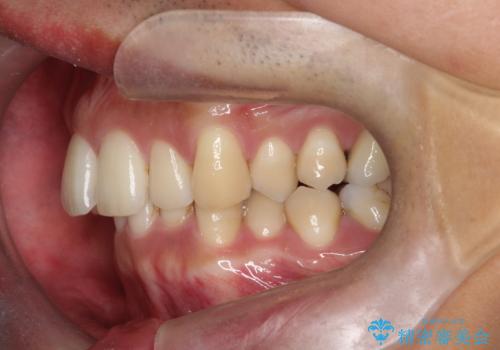

- 前歯のデコボコ(叢生)と、上下の歯の重なりが深い「ディープバイト(過蓋咬合)」を主訴にご来院されました。精密検査の結果、歯が並ぶスペースが不足しているため、上顎左右の小臼歯を抜歯することでスペースを確保し、全体の咬み合わせを改善する治療計画を立案しました。これにより、見た目の改善だけでなく、過度な咬み合わせによって生じる歯や顎への負担も軽減することを目指します。

今回の矯正治療では、まず歯が並ぶスペースを確保するため、上顎の小臼歯を抜歯しました。抜歯によってできたスペースを利用して前歯を奥へ移動させ、デコボコを解消。同時に、奥歯の咬み合わせを調整することで、深すぎた咬み合わせであるディープバイトも改善しました。治療の結果、長年気にされていた前歯のデコボコが解消され、理想的な歯並びに。さらに、正しい咬み合わせを獲得したことで、機能的にも安定した美しい口元になりました。